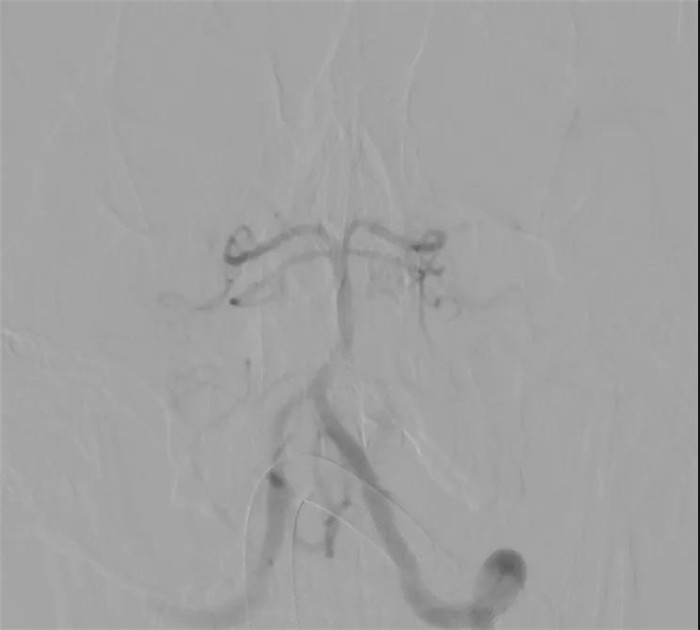

“复合手术室可以对手术患者进行血管造影检查,根据造影检查结果进行手术,并随时可以造影查看手术效果,不必再像以往那样先做造影,再进手术室手术,然后再推出手术室做造影。” 陈晓霖介绍,小豪的全脑血管数字减影造影显示,他的出血病灶是位于小脑蚓部的脑动静脉畸形,而且右侧小脑上动脉和双侧小脑后下动脉都参与了动静脉畸形的供血,动脉极其迂曲,不论是栓塞前的微导管超选还是栓塞后的微导管撤出都存在一定难度。

根据造影结果,医生们选择对右侧小脑上动脉和左侧小脑后下动脉进行栓塞以降低术中出血风险。由于动脉迂曲、活动度极大,微导丝和微导管的每一寸进退都冒着刺破动脉的风险,足足用了一个小时,两支目标动脉中病灶的供血分支和一部分病灶被成功栓塞,正常血管分支被完整保留。

“我建议尝试通过最后这支供血动脉争取完全栓塞,开颅只做血肿清除,尽量减少对脑干的影像。”陈晓霖说,大家随后对最后一支供血动脉发起“进攻”。通过不断调整微导丝的形态,将微导管超选到尽可能靠近畸形巢的位置,王明泽向微导管内推入栓塞剂。随着一团栓塞剂慢慢出现在引流静脉与病灶交界的位置,畸形完全被栓塞,经过造影复查,原本“一团乱麻”的病灶区域十分干净,只有几团栓塞剂的痕迹若隐若现,小脑的各个分支动脉都被完好保留!